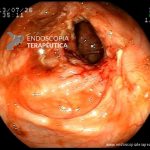

- Doença de Crohn em remissão – cicatriz